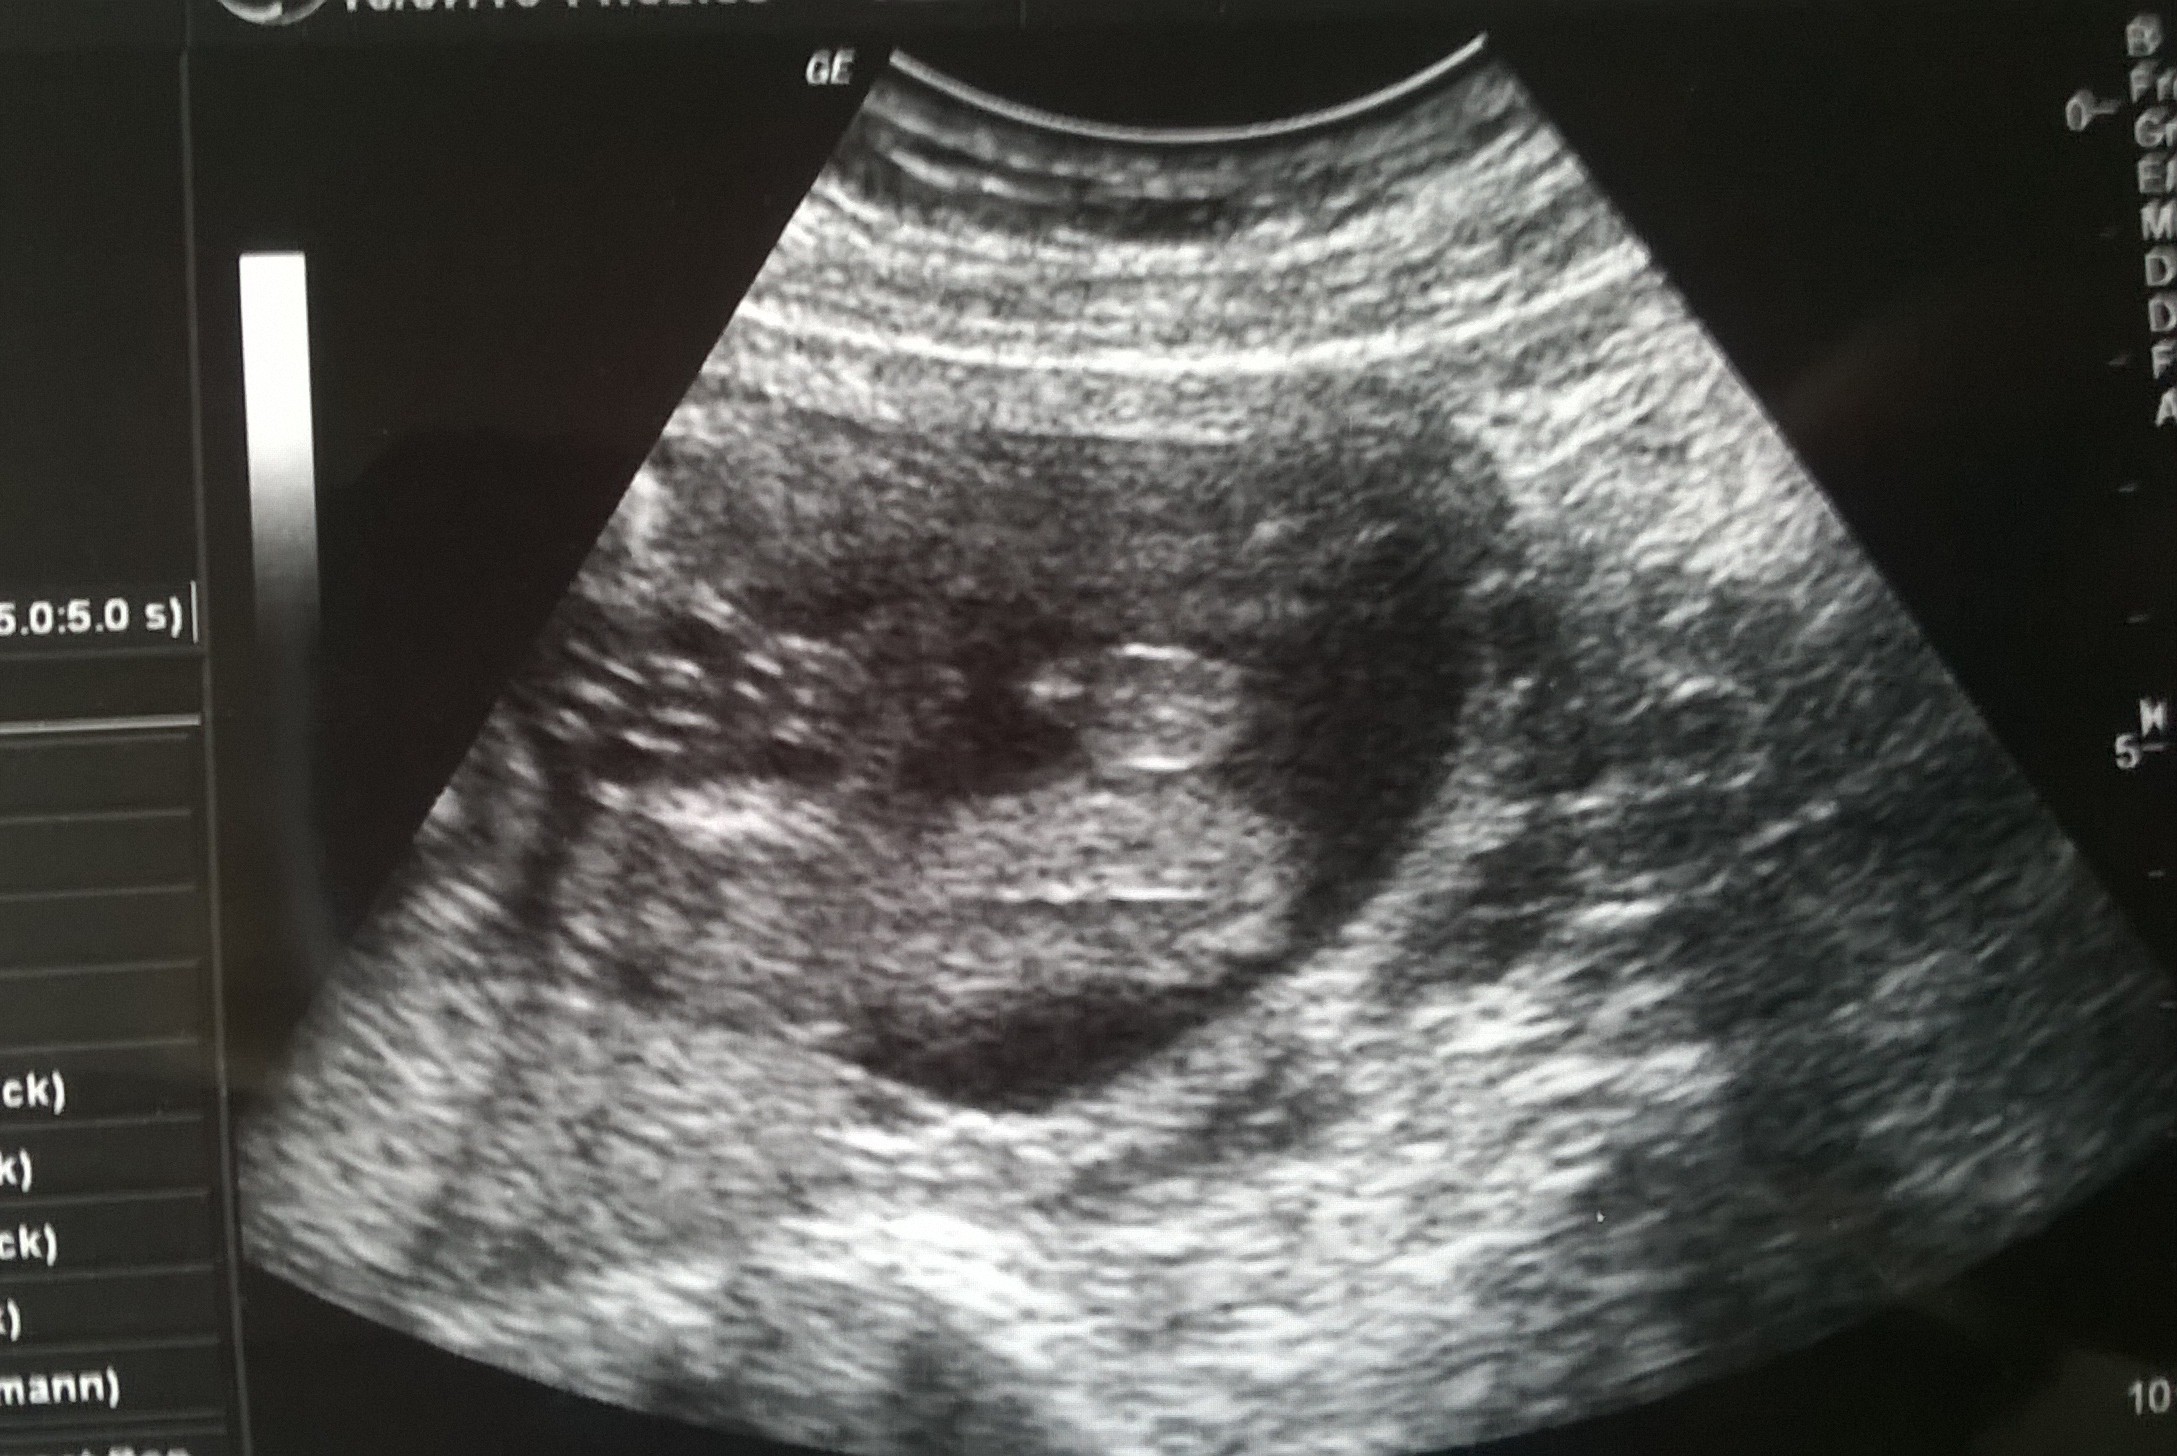

To u mnie od dolu tak jak u Karolina worek widac. Pindorek maly a w realu dlugi i cienki. No i u mnie masz gwarancje ze facet